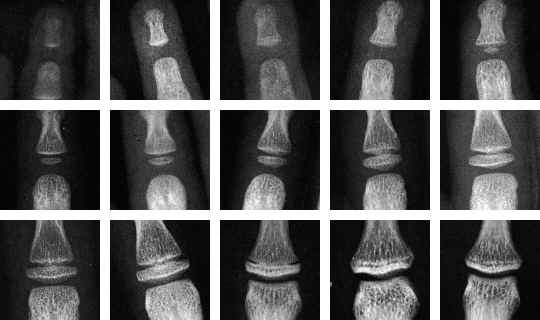

當然 how-old.net 不太可信,若想科學一點的話,有網民提議用 X-Ray 照一照手指骨驗一下